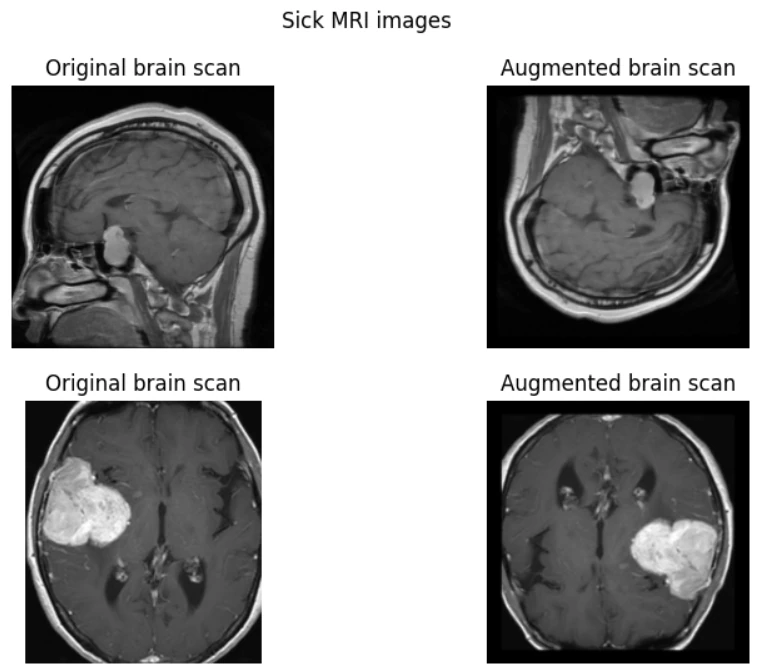

This brain tumor prediction model harnesses a fine-tuned CNN architecture, leveraging extensive data augmentation and rigorous preprocessing to achieve over 96% accuracy. Outperforming expert radiologists, it integrates advanced deep learning techniques with meticulous optimization to reliably detect and classify tumors. Designed for precision and efficiency, this model serves as a powerful diagnostic tool, supporting early detection and informed medical decisions in critical healthcare scenarios.